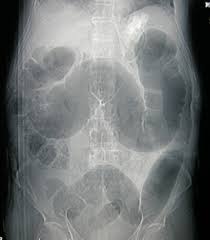

Can Colon Cancer Be Mistaken For Hernia : Female Hernias Can Be Misdiagnosed Or Overlooked Prime Surgicare : I was diagnosed in april2019, and had my first surgery on 5/6 (opensurgery), with a second one 10 days later due to an anastomotic leak.. Some of the other medical conditions that can be confused with appendicitis include: A hernia happens anytime a body part pushes into a place where it doesn't belong. It should not be mistaken for a pericolic abscess and, where there is the slightest doubt, percutaneous drainage should be contraindicated. Due to the widely misunderstood nature of cancer, cancer misdiagnosis is among the most common type of medical misdiagnosis. We therefore conclude that the association between colon cancer and inguinal hernia is mainly coincidental, and the cancer must be suspected on a clinical basis.

Pdf An Unusual Case Of A Strangulated Right Inguinal Hernia Containing The Sigmoid Colon from i1.rgstatic.net Shelby is very active on our site always there to help others along their way, offering support and answering questions that those who are just starting. It may lead to immediate death, so you have to know symptoms and early warning signs of colon cancer to protect yourself against this disaster. An inguinal hernia containing colorectal cancer is rare but serious and can often present with complications such as perforation. In this condition, pain is caused on the left side of the abdomen but it can also be at the right side, which is quite close to the location of the appendix. Because hernias are more common in men than in women, they can sometimes be an overlooked source of pain for women, according to the society of laparoendoscopic surgeons (sls). A hernia happens anytime a body part pushes into a place where it doesn't belong. A tumor is a solid or cystic mass. The use of synthetic mesh in association with colonic resection did not lead to post operative infection, allowing concomitant treatment of both diseases in elderly, high risk patients.

We therefore conclude that the association between colon cancer and inguinal hernia is mainly coincidental, and the cancer must be suspected on a clinical basis. Less than 1 out of 200 cases of crc is localized within an inguinal hernia 6 . It may lead to immediate death, so you have to know symptoms and early warning signs of colon cancer to protect yourself against this disaster. Colon cancer is a very critical issue and maybe one of the causes of sudden death in young men, women and elderly. I performed an scope examination of her esophagus and confronted a huge cancer occupying the lower portion of her esophagus. The use of synthetic mesh in association with colonic resection did not lead to post operative infection, allowing concomitant treatment of both diseases in elderly, high risk patients. In the region of the inguinal canal, where most hernias occur, there are lymph nodes that can enlarge from infectious or malignancies, and can be mistaken for a hernia. When a hernia meets cancer. A tumor is a solid or cystic mass. A female patient came to see me with some difficulty swallowing, a very routine issue for a gastroenterologist. When colon cancer is detected in its early stages, there may be no symptoms present at all. Typically, patients with ventral hernias describe mild pain, aching or a pressure sensation at the site of the hernia. As detailed in the risk factors, acid reflux caused by hiatal hernia is one of the main cause of esophageal cancer.

Although still considered rare, adenocarcinoma of the esophagus, the most common form of esophageal cancer, is one of the. Since a hiatal hernia often exhibits the same symptoms as other conditions, it can be easily mistaken for something else entirely. De caestecker discusses hernia symptoms and what they might be mistaken for. Initial common symptoms in patients presenting with colon cancer are abdominal pain, change in bowel habits, melaena, and general weakness 5 . Colonoscopy, a procedure which involves a flexible tube with an attached video camera. Some of the other medical conditions that can be confused with appendicitis include: In cases where cancer is not identified or mistaken for another disease, patients may miss a critical window for treatment. As detailed in the risk factors, acid reflux caused by hiatal hernia is one of the main cause of esophageal cancer. Many conditions can cause hip pain, and cancer is one of them. An inguinal hernia containing colorectal cancer is rare but serious and can often present with complications such as perforation. Less than 1 out of 200 cases of crc is localized within an inguinal hernia 6 . Do not hesitate to consult your cancer doctor immediately and visit a colon cancer center if you suffer from any of these warning signs. She is an endometrial cancer survivor and is starting to get compfortable with the idea of being a survivor.